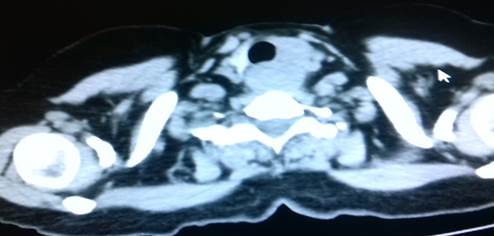

Pruebas de laboratorio: se aprecia leucocitosis en 12.000cel/mm3 y luego progresa a 24.500cel/mm3, polimorfo nuclear 90%, valores de glucosa en sangre elevada. Se le realiza rayos x de cuello (Figura 2. Anexos), y ecosonograma de región cervical, donde se describe una lesión ocupante de espacio alrededor de la tráquea hacia el lado izquierdo, de 4x 2 cm, heterogénea de bordes bien circunscritos. No presenta vascularidad al uso del Doppler. El lóbulo izquierdo del tiroides, muestra efecto de masa en su cara inferior. Concluye con una lesión ocupante de espacio en región traqueal izquierda sugerente de absceso frio. Se le realiza estudio de tomografía computarizada de cuello (Figura. 3, 4, 5. Anexos), y tórax, apreciando en región lateral izquierda del cuello, hiperdensidad paralela a la tráquea y glándula tiroidea, haciendo efecto de masa compresiva sobre las estructuras cercanas.

IMG_20181019_154930

Figura 5. Tomografía axial computarizada de región cervical. apreciando en región lateral izquierda del cuello, hiperdensidad paralela a la tráquea y glándula tiroidea, haciendo efecto de masa compresiva sobre las estructuras cercanas.

Fuente: Fotografía realizada por Dra. María Pulgar.